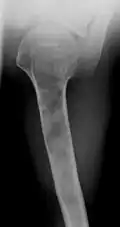

X-ray showing enchondromas localized in the lower part of the radius of a 37-year-old patient affected with Ollier disease -

| X-ray image showing enchondromas localized in the lower part of the radius of a 7-year-old girl with Ollier disease. | |